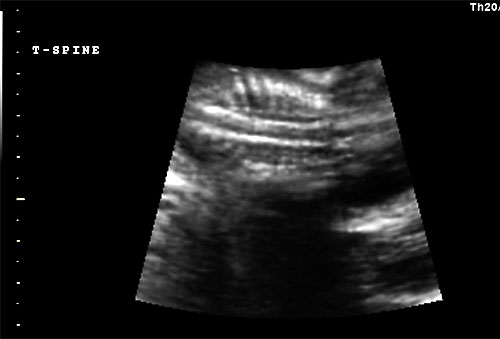

Normal 16 week sagittal view of thoracic spine |